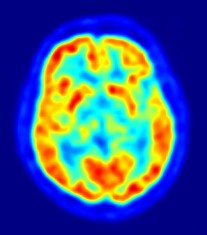

Des chercheurs de l'Université Bimghampton ont analysé les signaux du cerveau de 45 volontaires pendant qu'on leur lisait une liste de 75 acronymes, genre FBI, NSA, PLQ, INRS, etc. (OK, OK, il n'y avait pas INRS dans la liste). Ils ont enregistré la réaction du cerveau à chaque groupe de lettres en mettant l’accent sur la région du cerveau associée à la lecture et la reconnaissance des mots. Ils ont ainsi découvert que les cerveaux des participants réagissaient différemment à chaque acronyme, et ce, de façon persistante, assez pour que l'ordinateur puisse établir une "identité" pour chaque volontaire avec une précision de 94%. Ces résultats semblent donc indiquer que les ondes du cerveau seraient comme une empreinte digital, et pourrait être utilisée pour filtrer l'accès à votre compte Facebook, voire à des systèmes à haute sécurité.